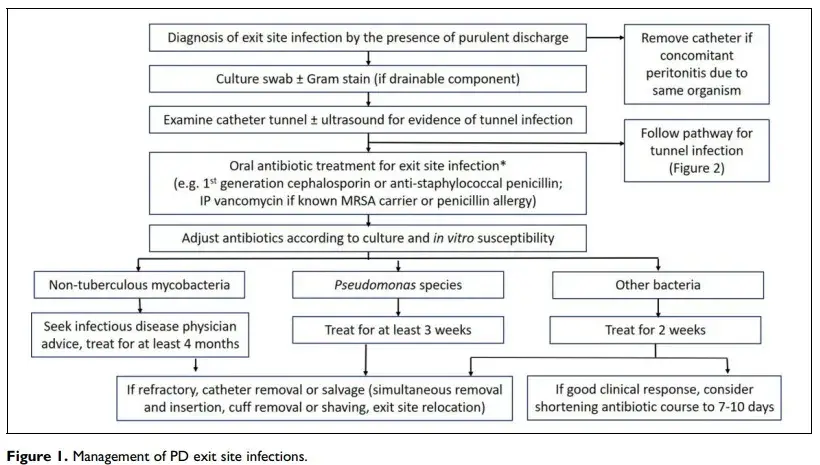

Antes de tudo é importante definir os tipos de infecções relacionadas ao cateter de DP:

### Infecção de Óstio

É considerado uma infecção definitiva do sítio de saída quando existe uma descarga de material purulento, com ou sem eritema na pele ao redor do cateter.

Se o paciente apresenta secreção pelo óstio devemos realizar cultura do _swab_ da secreção. A coloração do gram e identificação da bactéria pode nos auxiliar e guiar o tratamento.

Após avaliação do óstio e coleta de material para cultura devemos avaliar o túnel do cateter com atenção, realizar inspeção e palpação avaliando edema, dor, coleção que possam sugerir uma tunelite.

### Infecção do túnel

**Infecção do túnel** é diagnosticada quando existe evidência clínica de inflamação (eritema, edema, dor ou enduração), com o sem a presença de coleções ao longo do túnel do cateter.

### RECOMENDAÇÃO DE TRATAMENTO ANTIBIÓTICO DE FORMA EMPÍRICA

É recomendado o tratamento de infecção de óstio com antibióticos orais com cobertura adequada para _S. aureus_ (cefalosporina primeira geração ou penicilinas com cobertura para _S aureus_), exceto se o paciente possuir história prévia de infecção/colonização por _S. aureus_ MRSA ou _Pseudomonas_, neste caso deverá ser feito tratamento apropriado* (1C).

*Nestes casos deverá ser feito tratamento com vancomicina (ou clindamicina se cobertura) ou antibióticos antipseudomonas.

### RECOMENDAÇÃO SOBRE MONITORAMENTO E DURAÇÃO DO TRATAMENTO

1. A duração do tratamento antimicrobiano para infecção de óstio deve ser modificado conforme evolução clínica e resultado da cultura do swab (susceptibilidade _in vitro_) (2C).

2. **O tratamento da infecção de óstio deve ser mantido por 2 semanas**. Podemos reduzir o tratamento para 7-10 dias se resolução clínica da infecção na reavaliação clínica com 7 dias (2D).

3. Se a infecção for causada por _pseudomonas_ existe a recomendação de manter tratamento por no mínimo 3 semanas com antibiótico adequado (1C).

4. Se sinais de tunelite devemos manter tratamento por 3 semanas (1D).

Infecções de óstio refratárias em que não se identifica o agente bacteriano na cultura da secreção devemos suspeitar de micobactérias não-tuberculose (_M. fortuitum, M. abscessus e M. chelonae_), nestes casos devemos solicitar avaliação com coloração Ziehl–Neelsen. Estas são infecções de difícil tratamento, com necessidade de associação de antibióticos e tempo estendido de tratamento (4 meses). Guidelines IDSA orientam a necessidade de retirada de qualquer corpo estranho (isto é, troca do cateter de DP) diante de infecção por M. abscessos para otimizar resolução do quadro.

### RECOMENDAÇÃO DE INTERVENÇÕES CIRURGICAS PARA CATETERES DE DO INFECTADOS

1. Sugestão de retirada do cateter de DP em pacientes com infecção de óstio e/ou infecção de túnel que evoluam ou apresentem simultaneamente quadro de peritonite pelo mesmo organismo (**2C**).

2. Sugestão de troca do cateter (remoção e reinserção simultânea) com confecção de novo sítio de saída, e sob cobertura antibiótica, para casos em que não foi possível resolução da infecção de óstel/túnel apenas com terapia de antibióticos (2C).

3. Sugestão de evitar troca do cateter (remoção e reinserção simultânea) nos casos que o _cuff_ interno apresente envolvimento com o quadro de peritonite (2C).

4. Sugestão de procedimentos para salvar o cateter de DP podem ser tentados em situações específicas

5. Sugestão que a remoção ou raspagem do _cuff_ seja considerado em pacientes com extrusão do _cuff_ externo e infecção no local de saída refratária a antibióticos (2C).

6. Sugestão de realocação do local de saída pode ser considerado se infecção no local de saída refratária a antibióticos (2C).